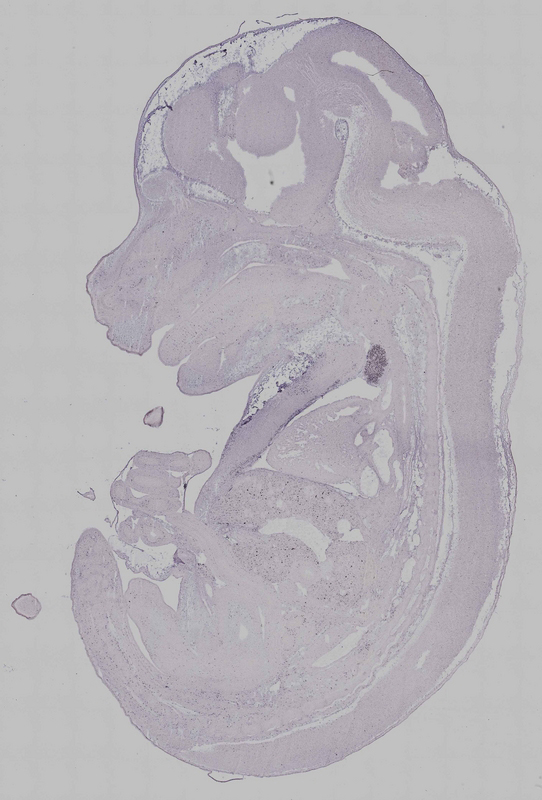

Reference: J:153498 Diez-Roux G, et al., A high-resolution anatomical atlas of the transcriptome in the mouse embryo. PLoS Biol. 2011;9(1):e1000582

Assay type: RNA in situ

Gene symbol: Fyb1

Gene name: FYN binding protein 1

Probe preparation: Antisense labelled with digoxigenin RNA

Visualized with: Alkaline phosphatase

Assay notes: Cryosections of fresh frozen material were fixed in 4% paraformaldehyde for 20 min. before further processing. A tyramide-biotin/streptavidin amplification step was included in the in situ hybridization procedure.

Specimen euxassay_013177_11: embryonic day 14.5 (more )

TS23: thymus primordium Strong Regionally restricted euxassay_013177_11